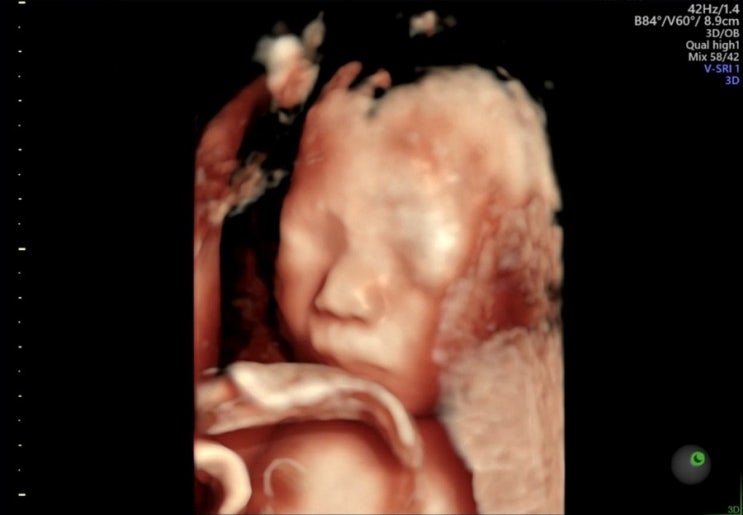

임신 25주차 | 미즈메디 임당검사, 입체초음파 후기

#임신25주차 #입체초음파 #임당검사후기 미즈메디 임신성당뇨(임당) 검사 나도 드디어 임당검사를 할때가 ...